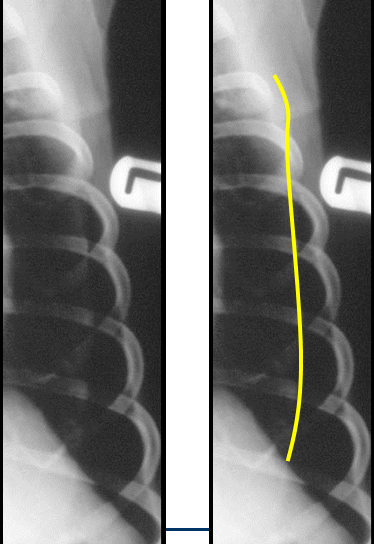

Discuss this radiograph?

Subcutaneous emphysema

Can get useful info about what has happened about changes going on within the thorax, VD of cat

Can see increase opacity and cannot see cardiac silhouette – but can see air and lucencies in subcut tissues

SUBCUTAENOUS EMPHYSEMA – suggests some kind of trauma and some leaking from airways at some point